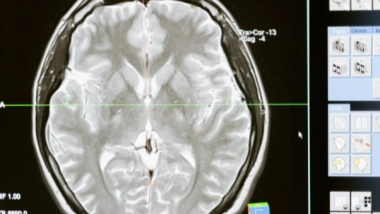

Washington [US], October 10 (ANI): A slew of new studies showed that the area of the brain responsible for initiating this action -- the primary motor cortex, which controls movement -- has as many as 116 different types of cells that work together to make this happen.

The 17 studies, appearing online in the journal Nature, are the result of five years of work by a huge consortium of researchers supported by the National Institutes of Health's Brain Research Through Advancing Innovative Neurotechnologies (BRAIN) Initiative to identify the myriad of different cell types in one portion of the brain.

It is the first step in a long-term project to generate an atlas of the entire brain to help understand how the neural networks in our head control our body and mind and how they are disrupted in cases of mental and physical problems.